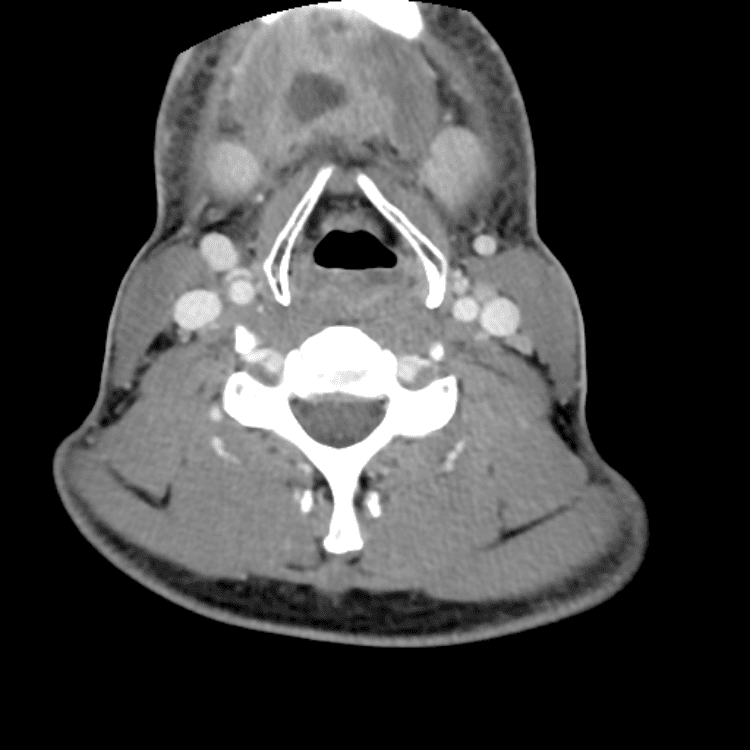

Head and Neck

Practice

Simulates call by including subtle or difficult cases and some normals.

27 cases